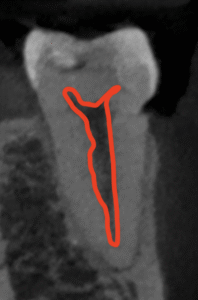

以下のように根管形成した。